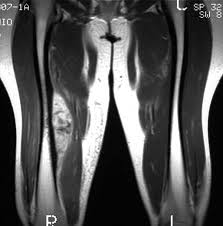

Efecto de una intervención individualizada de auditoría y retroalimentación sobre las tasas de solicitudes de diagnóstico por imágenes musculoesqueléticas por parte de médicos generales australianos

Entre los médicos generales australianos conocidos por solicitar con frecuencia imágenes de diagnóstico musculoesquelético, una auditoría individualizada y una intervención de retroalimentación, en comparación con ninguna intervención, disminuyó significativamente la tasa de pruebas de imágenes musculoesqueléticas dirigidas ordenadas durante 12 meses. JAMA, septiembre de 2022